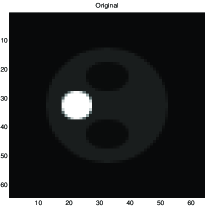

Fig. 8 shows results obtained in X-ray tomography image reconstruction. In this figure a) shows the original image, b) shows the projections (data), c) shows the backprojection reconstruction, d) shows a reconstruction using a Gaussian prior, e) shows a reconstruction using a Gamma prior, and f) shows a reconstruction using GNC with truncated quadratic regularization.

|

|

|

| a | c | e |

|

|

|

| b | d | f |

a) original, b) projections (data), c) Backprojection, d) Gaussian reconstruction, d) Gamma prior reconstruction, and e) GNC reconstruction